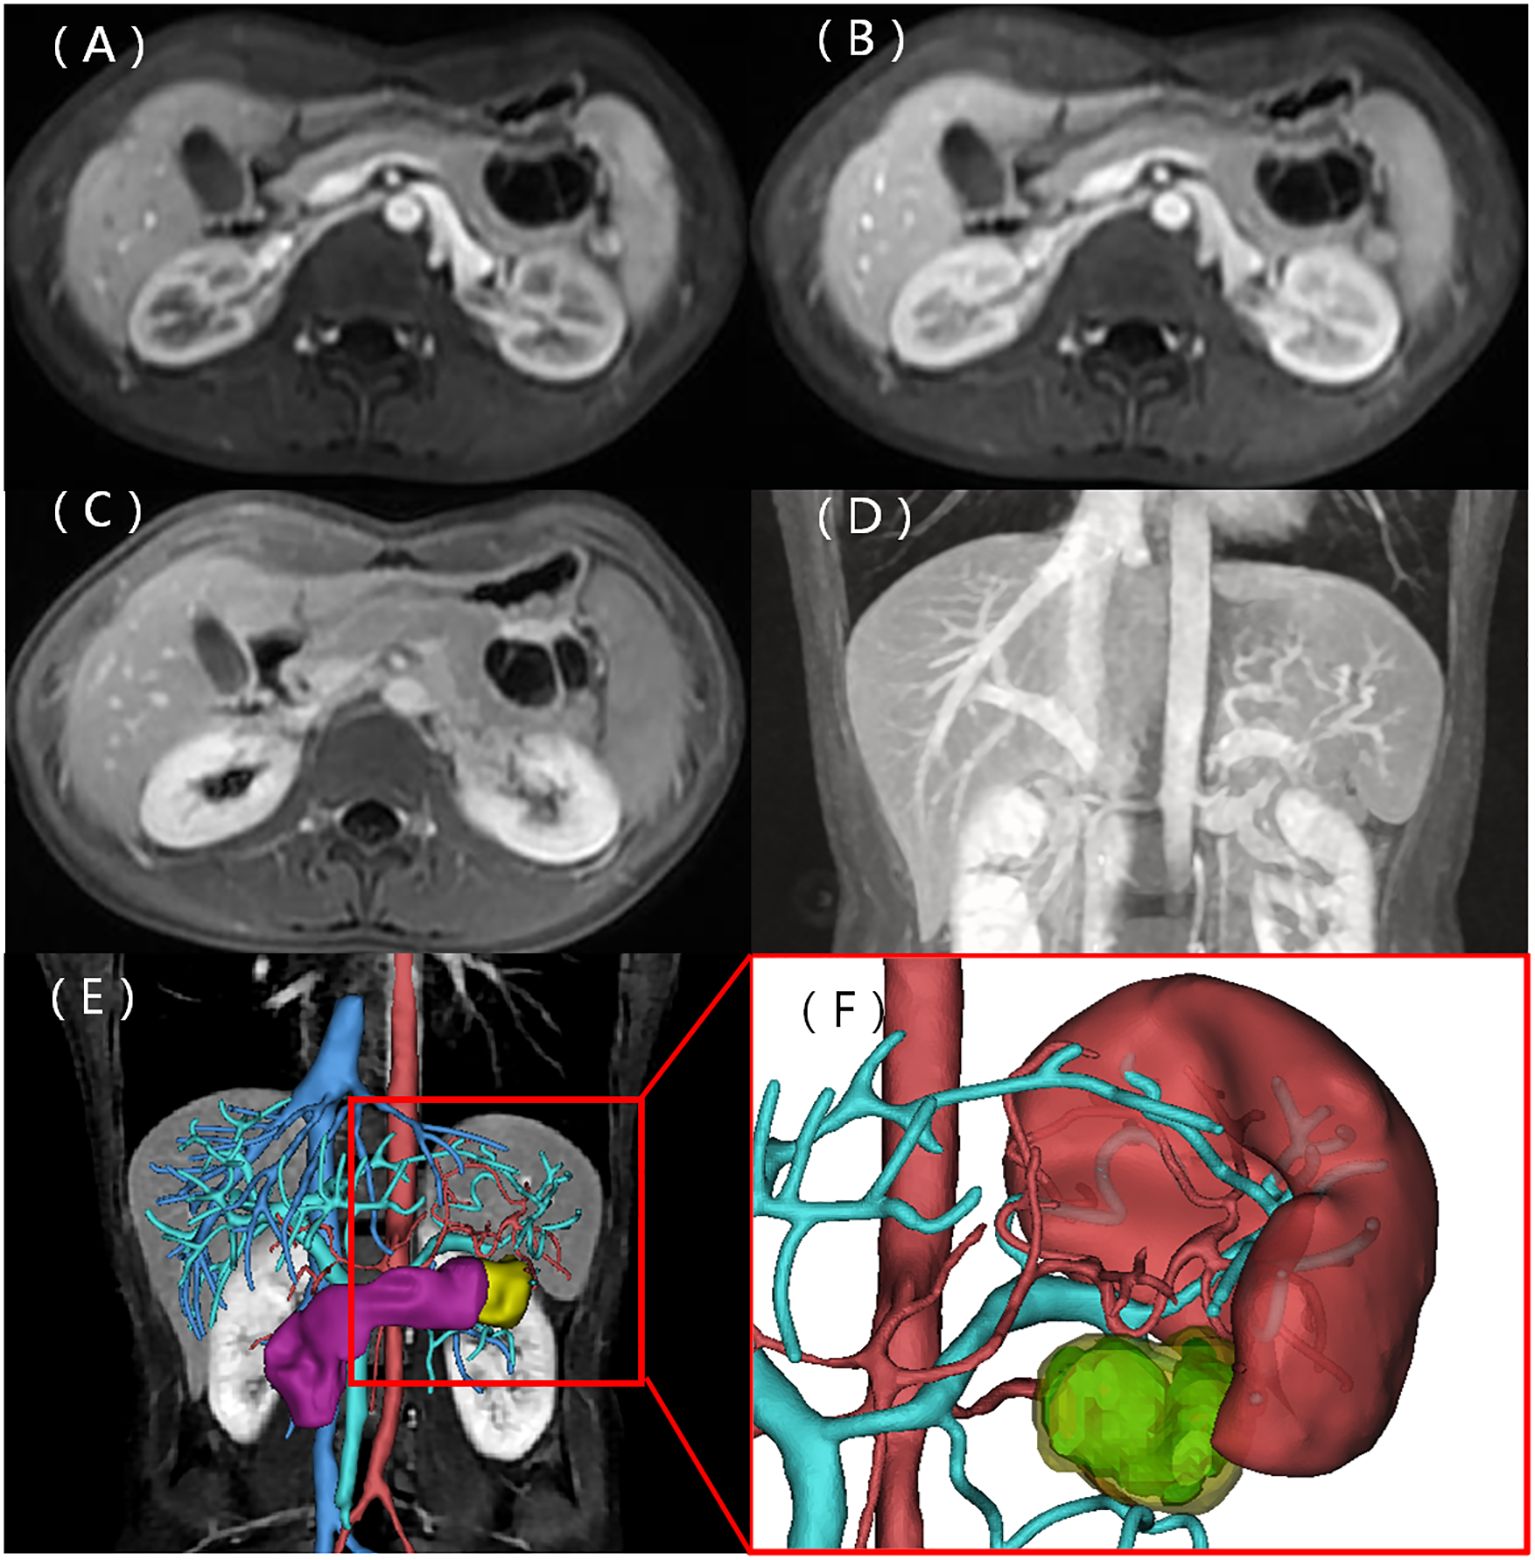

Figure 2

Medical imaging series of abdominal scans.   A: CT scan with a highlighted section showing a yellow arrow indicating a specific area of interest.   B to D: MRI scans with varying contrasts displaying different tissue and organ details in the abdominal region.   E: Diffusion-weighted MRI showing tissue density variations.

Figure 2. A CT scan identified a cystic-solid mass in the body and tail of the pancreas. The mass exhibited a regular shape, with solid components having equal density and septa, not clearly demarcated from the stomach (represented by the yellow arrow) (A). MRI T1WI shows solid components, with the septa appearing isointense, while the cystic components were hypointense (B). T2WI illustrates lightly hyperintense solid components and septa with hyperintense cystic components (C). A diffusion-weighted image depicts the solid components and septa as hyperintense (D) and hypointense on the ADC map (E).

A 22-year-old woman was admitted to the hospital in August 2022 after a routine medical checkup revealed a cystic-solid mass in her pancreas. The patient’s past medical history, personal history, and family history were unremarkable. Physical examination of the abdomen revealed no notable findings. An ultrasound revealed a cystic mass in the tail of the pancreas with clear margins, multiple hyperechoic septa, and isoechoic nodules at the edge (Figure 1). Furthermore, a computed tomography (CT) plain scan revealed a cystic-solid mass in the body and tail of the pancreas, which appeared regularly shaped with solid components of equal density and septa (Figure 2A), measuring approximately 3.6 × 2.5 cm. There was no clear demarcation of the lesion from the adjacent organs and the peritoneum. To further assess the nature of the lesion, the patient underwent magnetic resonance imaging (MRI). The MRI findings revealed a cystic-solid mass in the body and tail of the pancreas with septa. The solid components and septations appeared isointense on the T1-weighted image (T1WI), while they were slightly hyperintense on the T2-weighted image (T2WI). The cystic components were hypointense on T1WI and hyperintense on T2WI (Figures 2B, C). The lesion was found to adhere tightly to the adjacent organs and the peritoneum. On diffusion-weighted imaging (DWI), the solid components displayed hyperintensity (b = 800 s/mm2) and hypointensity on the apparent diffusion coefficient (ADC) map (Figures 2D, E). Gadolinium-enhanced scanning revealed a slight enhancement of the solid components and septa in the arterial phase (Figure 3A), followed by continuous enhancement in the venous and delayed phases (Figures 3B, C). However, the cystic component did not display enhancement. The maximum intensity projection (MIP) image indicated an enlargement of the portal vein and tortuous dilation of blood vessels in the splenic hilum (Figure 3D). Moreover, Figures 3E, F display the preoperative three-dimensional MRI of the tumor and adjacent structures. The preoperative diagnosis was a solid pseudopapillary tumor of the pancreas.